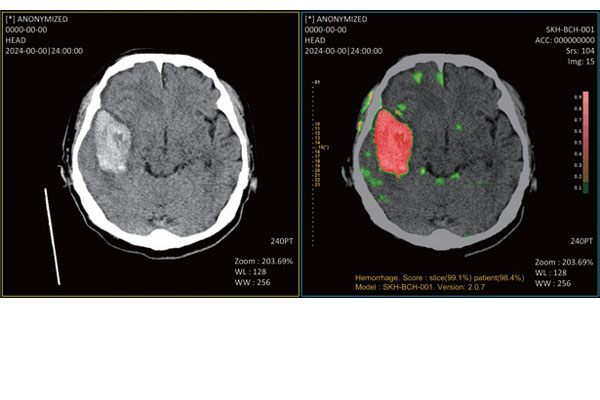

- 뇌출혈, 뇌경색 등 중증 뇌졸중 진단에 특화된 AI 기반 소프트웨어 의료기기 개발

- 뇌 CT 이미지 기반 AI 분석을 통해 의료진의 진단 속도 및 판독 정확도 향상

- 2023.09 비조영증강 CT (non-contrast computed tomography)를 사용한 인공 지능(AI) 기반 뇌출혈 검출 솔루션

인증 및 수상- 2021.08 뇌출혈 진단 보조 AI Medical Insight+Brain Hemorrhage, 식약처 3등급 의료기기 허가 획득

- 2024.05 뇌출혈 진단 보조 AI Medical Insight+Brain Hemorrhage, 식약처 혁신의료기기 수가 지급 기준 지정

- 2024.07 뇌출혈 진단 보조 AI Medical Insight+Brain Hemorrhage, 미 FDA 510(k) 승인